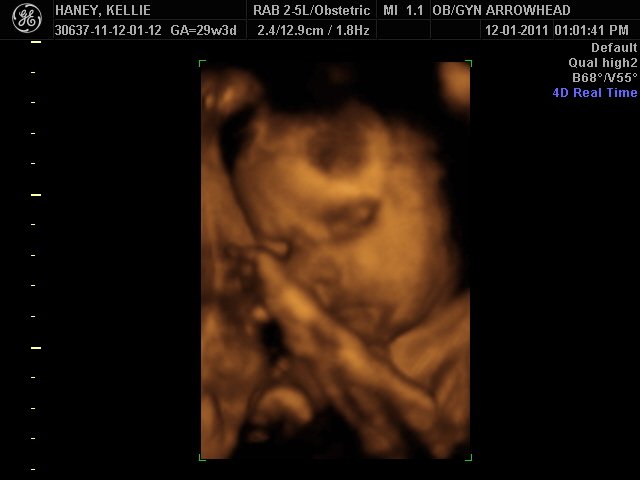

We offer complimentary 3D/4D Ultrasounds to all our OB patients around 30 weeks! The following photos are some examples of our work, shown with permission from our patients.